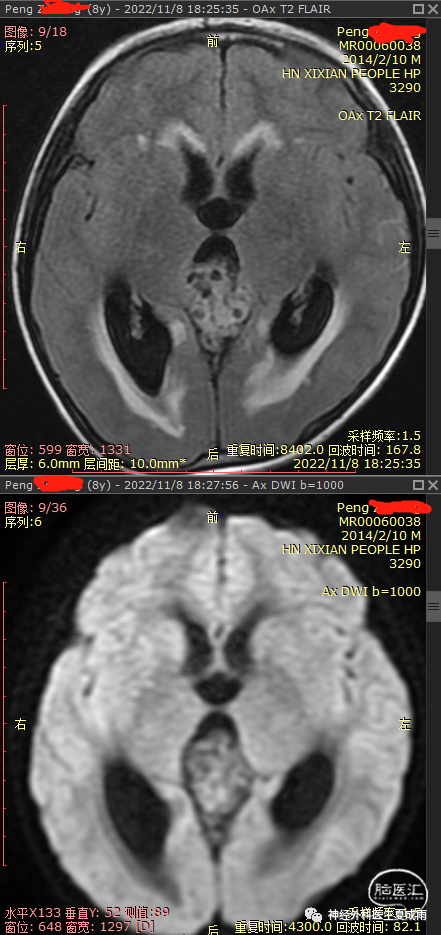

外院磁共振⏬

根据术前影像有钙化,强化不均匀,无尿崩,以及血清AFP增高,考虑为非生殖细胞瘤的生殖细胞肿瘤,建议首选行肿瘤切除术。